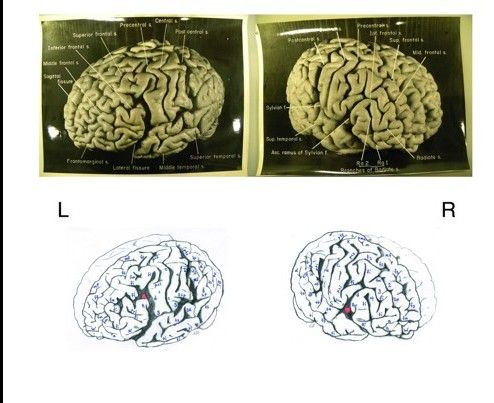

近期对14张新发现的爱因斯坦大脑切片进行的研究显示,这位大科学家的大脑的确在很多方面是与众不同的。这些大脑切片是当初在爱因斯坦去世之后被保留下来用作研究之用的。不过,科学家们目前仍然不清楚爱因斯坦大脑中所显示的那些额外的褶皱和沟回究竟是如何转化为爱因斯坦惊人的思维能力的。